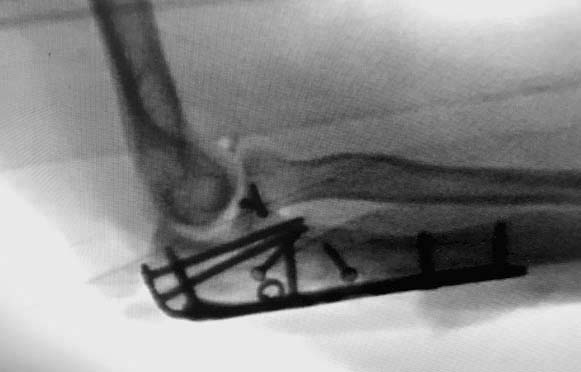

А так, здесь имеется многофрагментарный проксимальный перелом локтевого

отростка с переломо-вывихом головки лучевой кости по классификации Mason

III. Решение принимается на основании КТ срезов, потому что на боковом

рентген снимке вроде отсутствует смещение, где сустав и контур Coronoid

в одном блоке, а на прямом подозрение на смещение в Coronoid?

Для перелома локтевого отростка придуманы много пластин, надо выбрать по

длине. А при краевых переломах головки ее окружность можно восстановить

винтами 2 мм, но в данном случае имеется полный вывих головки и

фиксация, даже специальной пластиной, может осложнится. Протез головки

после удаления предупреждает нестабильность в суставе и деформацию оси

конечности в будущем!

Конверсионные спицы на уровне проксимального отдела лучевой кости

интересная идея, но на уровне перелома в области шейки трудно удержать

головку. Предварительная репозиция локтевого отростка с временной

установкой пластины, затем удаление экономит время. Доступ через

локтевой отросток, где можно фиксировать или удалить головку с

замещением, а потом установить пластину обратно на локтевой отросток!